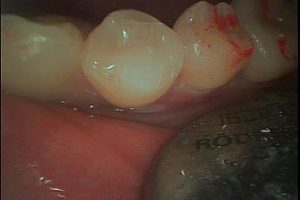

小内先生に麻酔してもらい、6倍の拡大鏡の元で歯に詰まっているプラスチックを削っていってもらうと・・・

ありました! ヒビが!

小さいクラックといわれるヒビですが、これが原因でした。クラックを削り、

最後はダイレクトボンディングで治してもらい。痛みも無くなりました。

これ全部、僕の歯のクラックが原因の歯の痛み→ダイレクトボンディングで一回で痛みも無くなり歯も白く治った写真です。

小さいヒビ(クラック)はなかなか裸眼ではわかりませんが、黒田クリスタル歯科 吉祥寺ではドクター全員 拡大鏡を使い診療しておりますので、ご安心して受診いただけます。